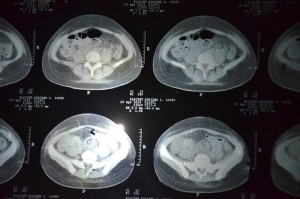

No atendimento a médica Maria do Socorro disse que no período que a paciente ficou no Hospital Regional de Sousa, ela foi atendida por outros sete médicos e fez vários exames. “Ela foi medicada, foram realizados exames laboratoriais que deram resultados normais, e o último exame de ultrassonografia mostrava líquido no interior do abdômen, foi feito uma tomografia, endoscopia, entre outros. Ela foi atendida por outros seis médicos, e apresentava uma melhora na redução do líquido”, falou.

Vários exames médicos foram realizados em Sousa (Foto: Diário do Sertão)